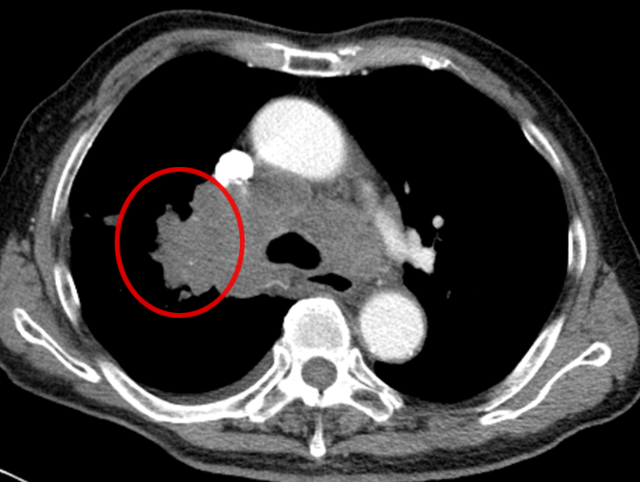

臨床上曾遇到一位 80 歲的老先生,1 年多前做過結腸癌手術,病理提示為 “低分化腺癌”,術后也完成了輔助化療。近期復查 CT 時,醫生發現他的右肺門長了新東西!

從 CT 影像看,這個右肺門腫塊高度懷疑是惡性腫瘤。但問題來了:老先生有結腸癌病史,這個肺腫塊是新長的肺癌(原住民),還是結腸癌轉移到肺部(移民者) ?

要知道,這兩種情況的治療方案截然不同,必須先明確 “腫瘤君的身份”。

起初,常規思路是做氣管鏡檢查取病理,但完善肺功能檢查后發現,老先生有重度阻塞性肺通氣功能障礙(相當于呼吸系統 “交通堵塞”),根本耐受不了氣管鏡。好在這個腫塊雖然位置特殊,但體積較大、離胸壁較近 —— 和患者及家屬充分溝通后,醫生決定采用 “CT 引導下經皮肺穿刺活檢”。

操作很快完成,術中術后都沒有出現血氣胸,老先生精神狀態良好,也沒覺得胸悶胸痛。3 天后病理報告出來了:小細胞癌!原來這不是結腸癌肺轉移,而是老爺爺患上了第二種原發腫瘤,是肺里地地道道的 “原住民”。